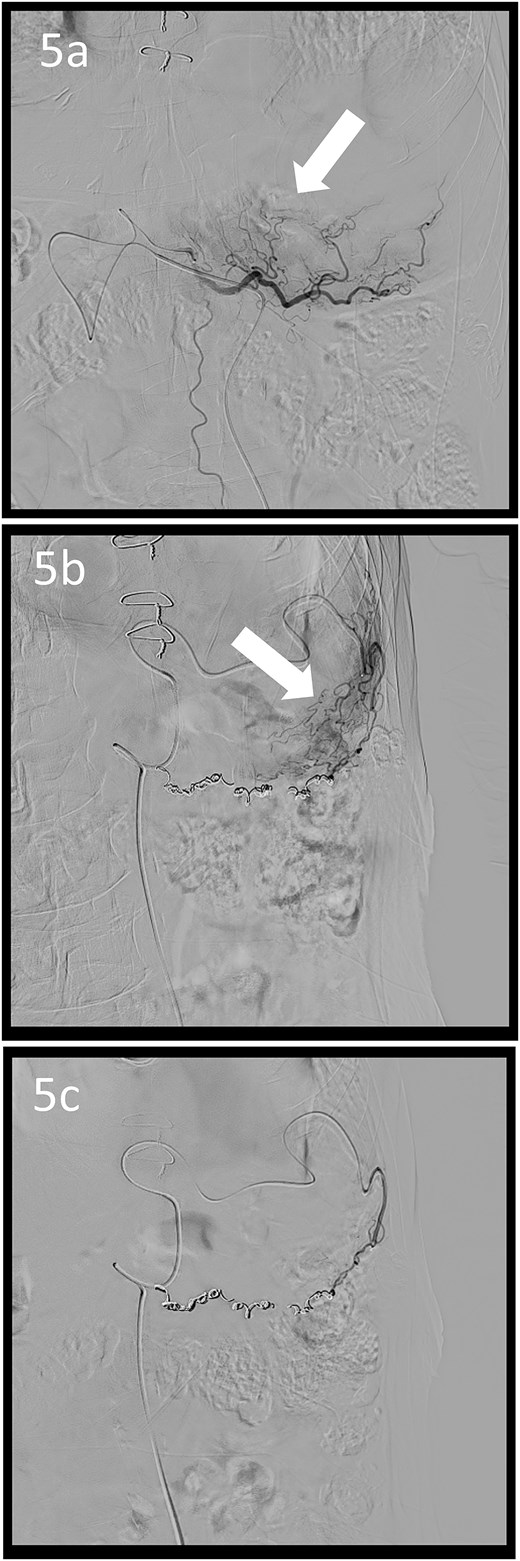

A 78-year-old man was transferred to our hospital because of hypovolemic shock. He had already received 10 units of RBC concentrate. His blood pressure was 97/64 mmHg. The patient’s haemoglobin level was 8.2 g/dL. Contrast-enhanced CT showed active contrast extravasation in the stomach (Fig. 4). Emergency angiography revealed tumour staining in both the left and right gastroepiploic arteries, which were coil embolized (Fig. 5). Upper GI endoscopy 2 days later revealed a type 4 tumour without bleeding (Fig. 6). The patient was diagnosed with resectable GC, and underwent laparoscopic total gastrectomy with Roux-en-Y reconstruction and lymph node dissection. The final histopathological diagnosis was T4aN3aM0 stage IIIC. Macroscopic findings revealed a type 4 tumour of the stomach, and histopathological findings revealed that the tumour was a poorly differentiated adenocarcinoma with squamous cell differentiation. All surgical margins were negative. The patient developed a minor leakage that resolved spontaneously. The patient has remained recurrence-free for 12 months.

Angiographic images; the right (a) and left (b) gastroepiploic arteriograms showing tumour staining (arrows); (c) both arteries were coil embolized.